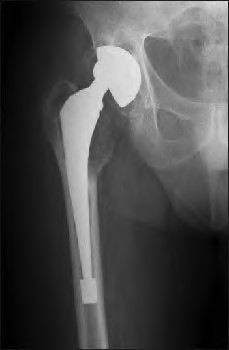

The radiograph demonstrates a periprosthetic femur fracture extending to the tip of the stem. The long spiral fracture is consistent with a loose implant. The bone stock is sufficient. Therefore, this fracture pattern would classify as a B2 using the Vancouver classification system. The Vancouver classification for periprosthetic femoral fractures is simple yet incorporates all the pertinent factors such a location, stem fixation, and bone stock. Type A is a trochanteric fracture- lesser or greater. These can be treated non-operatively usually and ORIF if symptomatic. Type B fractures are around or just below the stem and are subdivided into three types. Type B1 is a fracture with a well fixed stem.

The treatment is cable plating or allograft struts or a combination of the two. Type B2 is a fracture with a loose stem with good bone stock. The treatment is a cementless porous coated long stem atleast two diameter length past the

fracture site. Type B3 is a fracture with a loose stem and comminution. For younger patients, use cementless porous coated long stems with allograft struts. For older patients, consider a tumor prosthesis. Cement fixation is sometimes necessary Type C is a fracture well below the stem tip. These can be treated independently of the prosthesis.

Figure A shows a lytic lesion of the proximal femur with an intramedullary implant. Figure B shows a proximal femoral replacement.